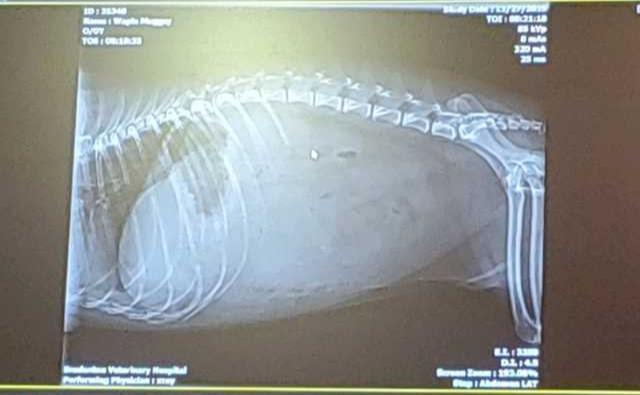

My 5 yr old male Boston terrier died the day before Thanksgiving. He was very lethargic, not eating much, looked bloated in his abdomen, had a fever for a day, some vomit and diarrhea. He was drinking water fine though. This lasted a few days and we took him into the vet. I attached the scan of his belly below. I guess all that solid greyish/whitish area where you can’t see bones anymore was some type of material/object. I had to leave that vet and take him to the ER.

Thnk you for submitting your question regarding Mugsy. I am so sudden for his sudden loss. That is difficult to bear any time, but especially with a dog so young. An impacted anal glad could not result in the symptoms you have described. So I do not believe his scooting was part of the disease process. It is difficult to tell from the x-ray, but I worry there is fluid in his abdomen as there is poor detail. It is difficult to make out specific internal organs. Fluid can be from an infection, bleeding or significant GI, liver, heart or kidney disease. Regardless of the cause, he was very sick and the outcome likely would not have been different with anything you could have done. Again, I am so sorry for your loss.